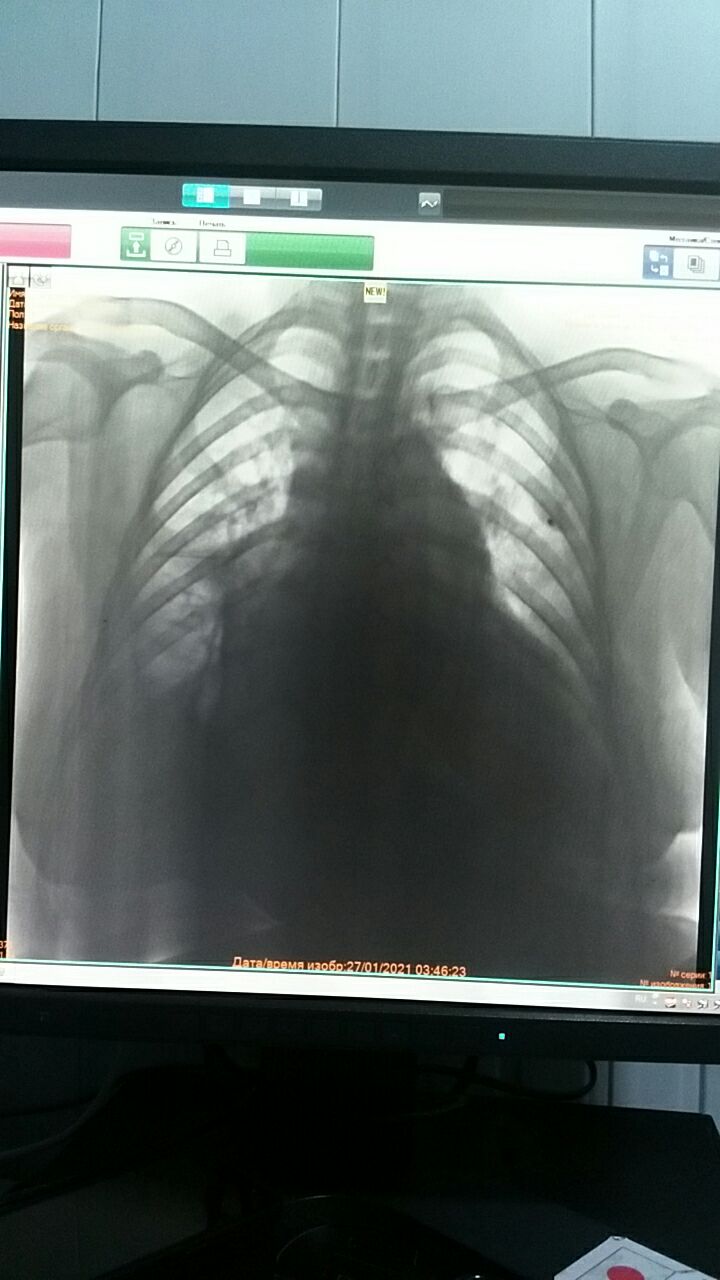

Здравствуйте Коллеги ! Пациент 1973года, с правосторонним ОНМК

Пол: жен.

Каков ваш R-диагноз ?

Осумкованный плеврит справа паракостальные наслоение н/д правого легкого

Снимок лëжа сделан? Правосторонний гидроторакс. Кардиомегалия. Синдром фокусной тени слева. Рекомендовано КТ

Пациент в сидячем положении. Спасибо

Застарелый перелом по моему ребра и тень от дроби

Согласна, но видно плохо и для этого нужно анамнез уточнить или хотя бы вторую проекцию сделать